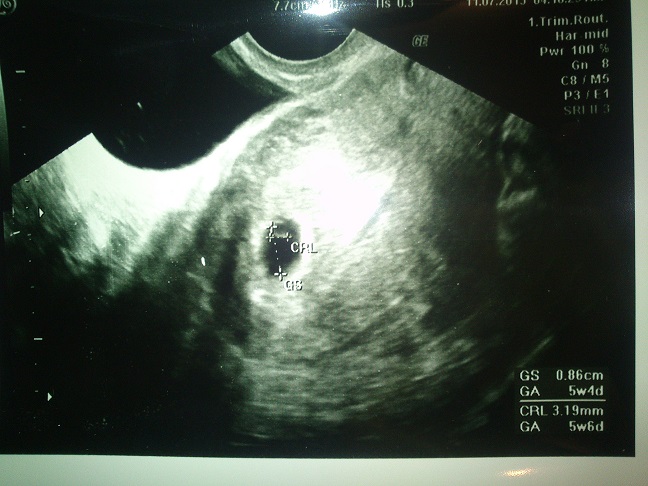

nasa miska bude na svete 3,3 2014

nasa malickaMiška ma 1800g a budem rodit znova cisarskym

budeme mat dievcatko na 100percent